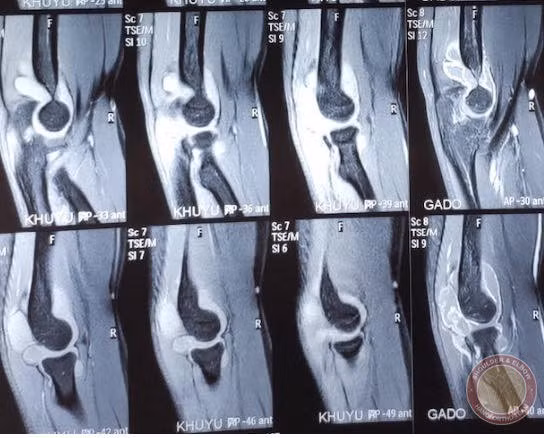

| Hình ảnh phim chụp (BVCC). |

Ngày 3/10/2019 anh T đến khám tại BV Đa Khoa Xanh Pôn, được bác sĩ Nguyễn Hữu Mạnh khám lâm sàng. Lúc khám ban đầu, bác sĩ nhận thấy khuỷu tay phải của bệnh nhân sưng đau bất thường và có biểu hiện kẹt khớp. Bác sĩ đã cho bệnh nhân chụp phim cộng hưởng từ để tìm nguyên nhân.

Bệnh nhân được chẩn đoán bệnh u sụn màng hoạt dịch. Đây là một dạng dị sản lành tính của bao hoạt dịch trong đó các tế bào liên kết có khả năng tự tạo sụn.